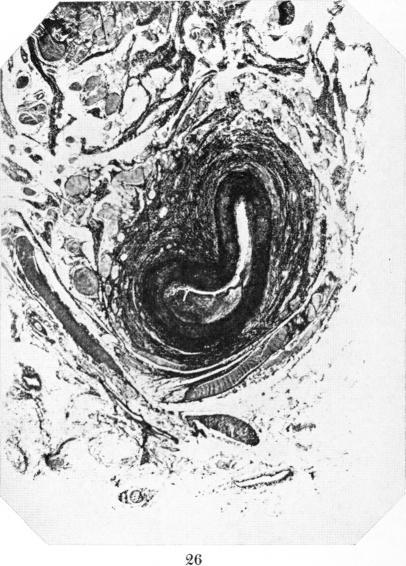

Studies in the Pathology of Rheumatic Fever: Two Cases Presenting unusual Cardiovascular Lesions.

Am J Pathol. 1927 Nov;3(6):583-594.19.